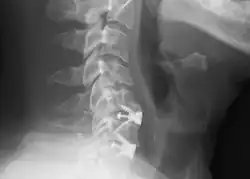

![]() X-rays of anterior cervical discectomy and fusion, C5C6 and C6C7. Lateral view. | |

To prevent the vertebrae from collapsing and to increase stability, the open space is often filled with a graft. That can be a bone graft, taken from the pelvis or cadaveric bone; or an artificial implant.[4] The slow process of the bone graft joining the vertebrae together is called "fusion". Sometimes a titanium plate is screwed on the vertebrae or screws are used between the vertebrae to increase stability during fusion, especially when there is more than one disc involved.